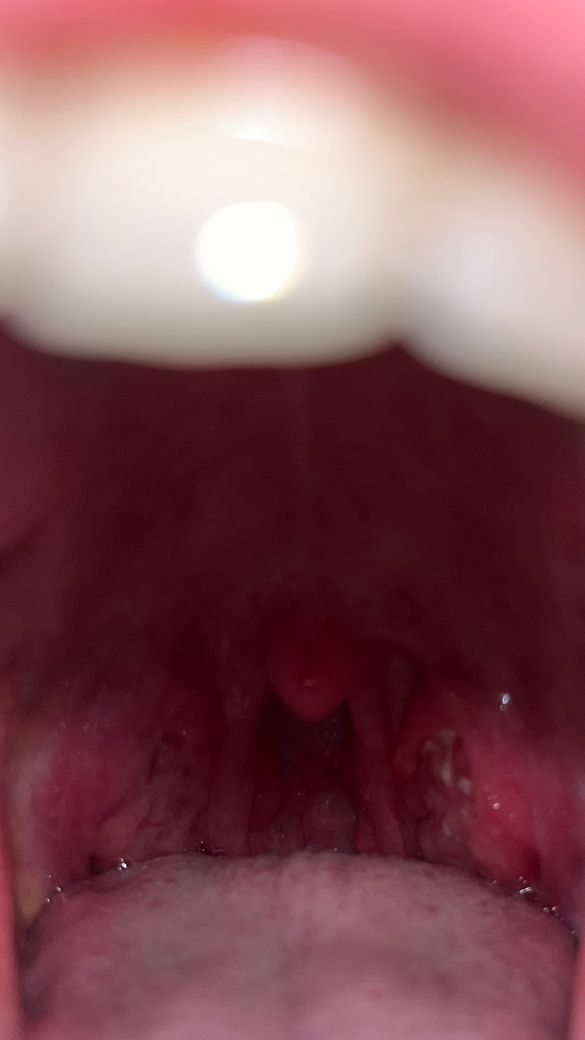

편도쪽에 하얗게 뭐가 올라왔어요

사진상 오른쪽)

편도결석인 줄 알고 양치하면서 빼보려고 했는데 빠지진 않고... 염증이라기엔 통증도 1도 없고 느낌도 안나요 그리고 하얀거 밑에 쪽이 살짝 반대편에 비해 부어있는데 괮찮은걸까요?

염증반응으로보입니다.

통증은 없더라도 편도가 붓고 염증이있는것으로 보아 가까운 이비인후과진료를 보고 치료를 받으시는것이 좋겠습니다.